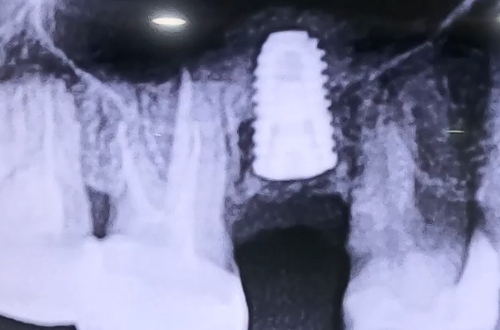

상악동거상술 임플란트 사례

AFTER

뼈이식으로 묻어둔 임플란트는 단단히 굳어 자리를 잡기까지 6개월 정도 기다린 후,

보철이 완성되면 다음 진료일지로 찾아뵙겠습니다. ^^